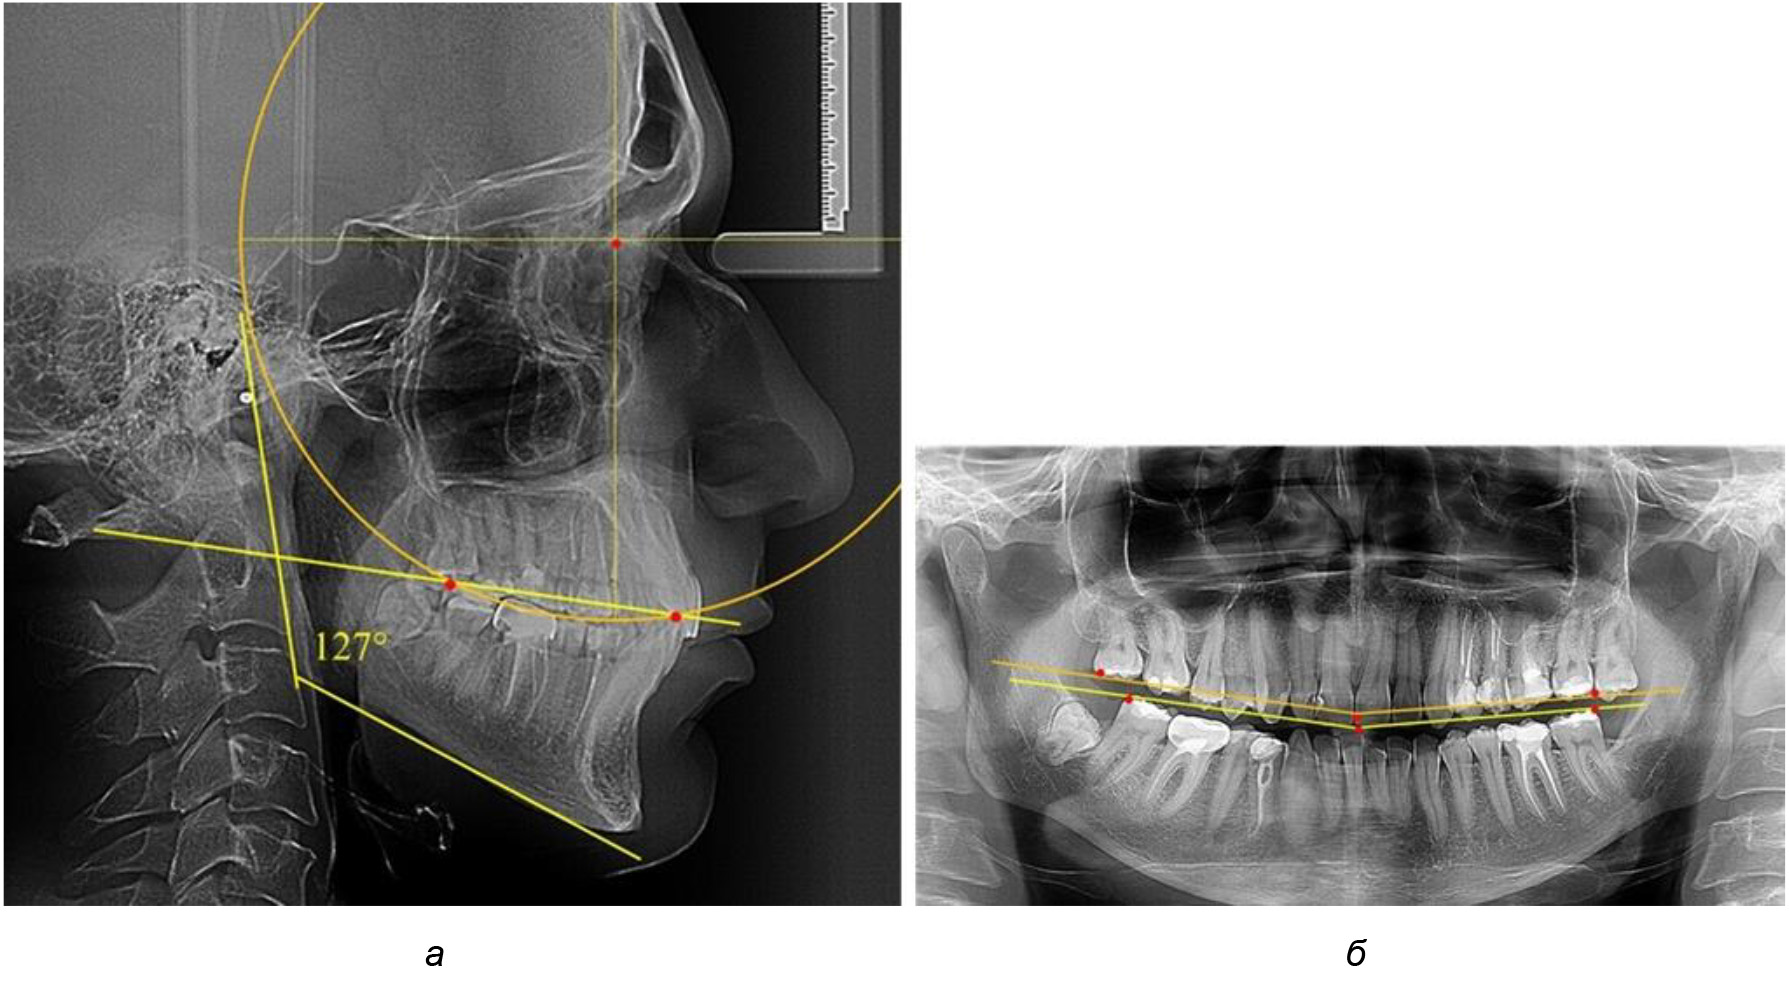

В ходе исследования установлено, что в 1-й подгруппу вошли ТРГ и ОПТГ 18 человек 1-й группы, что составило (29,03 ± 5,78) % от всех пациентов, рентгенограммы которых были проанализированы. У всех пациентов величина угла нижней челюсти была более 125° и в среднем составила (129,89 ± 3,62)° и характеризовала вертикальный тип нижней челюсти.

Учитывая существенную вариабельность линейных показателей, обусловленных типологическими (гнатическими и дентальными) вариантами зубочелюстных дуг, анализ проводили только при измерении глубины кривой Spee в наиболее углубленном месте и оценивали относительный показатель через отношение радиуса круга к сагиттальному расстоянию окклюзионной линии.

Анализ результатов показал, что глубина кривой Spee в среднем по подгруппе составил (4,12 ± 0,53) мм как при анализе ТРГ, так и ОПТГ.

Деление величины радиуса круга к длине окклюзионной линии составило 1,623 ± 0,02. Таким образом, для определения радиуса окружности, соответствующей кривизне окклюзионного контура боковой ТРГ, необходимо измерить расстояние между передней и задней окклюзионными точками и последующим умножением полученной величины на число Фибоначчи (рис. 2).

Рис. 2. Особенности кривой Spee на ТРГ (а) и ОПТГ (б) у людей с признаками вертикального роста